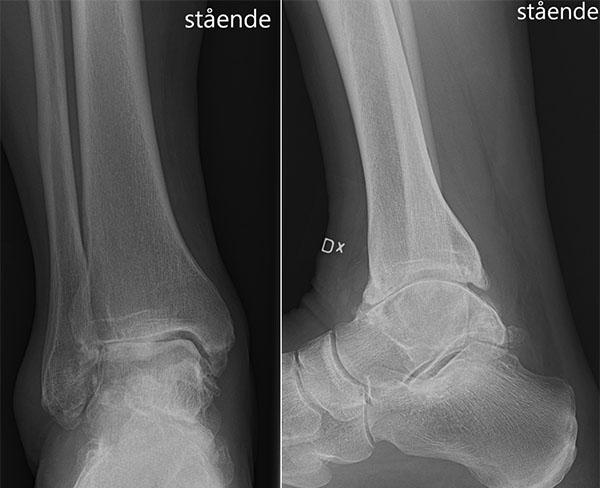

Dessa båda typer av höftfraktur kommer att undersökas inom ramen för två registerbaserade randomiserade studier. Dislocerad (t.v.) respektive odislocerad collumfraktur (t.h.).

ÄR HÖFTPROTES HIPPARE ÄN SKRUV? OCH ÄR DUBBELCUPPAR BÄTTRE ÄN STANDARDCUPPAR?

Vi tror oss veta att dubbelcuppar minskar risken för luxation, men evidensen bakom detta är svag, och även här krävs en brett anlagd studie på ett tusental patienter för att kunna svara på frågan. Redan nu har 14 ortopedkliniker som idag använder dubbelcuppar på frakturpatienter visat intresse för att ansluta sig till ”DUALITY”-studien. Inklusionen ska ske på exakt samma sätt som i HipSTher-studien, fast nu plingar det istället till när man har lagt in en patient med collumfraktur grad 3 eller 4 enligt Garden.

En kollektiv insats av nästan hela landets ortopedkliniker, Svenska frakturregistret och Svenska höftprotesregistret behövs för att tackla en spännande fråga som är hett diskussionsstoff på röntgenronder: Ska även odislocerade collumfrakturer på äldre patienter opereras med protes? Med tanke på att risken för haveri eller caputnekros efter osteosyntes ligger på upp till 18% även på odislocerade frakturer kan det vara värt att fundera på om inte alla collumfrakturer på äldre borde protesförsörjas. Därför är nu en stor register-RCT under kodnamnet ”HipSTher” på väg att startas, med målet att inkludera drygt 1.000 patienter med höftfraktur. Upplägget är så enkelt som möjligt: Registrerar man in en patient med diagnoskod S72.00 och felställning grad 1 eller 2 enligt Garden i frakturregistrets inmatningsplattform kommer det att plinga till, och man kommer att tillfrågas om man vill inkludera patienten i studien. Då ska man helst svara JA! — går och inhämtar patientens samtycke, och trycker sedan på nästa knapp som ger en randomisering till antingen osteosyntes eller protes. Studien är pragmatisk, så val av skruv eller spik, respektive halv- eller helprotes, är helt upp till operatören.

I ”HipSTher”-studiens kölvatten seglar nästa register-RCT upp, dock nu på frågan om dubbelcuppar verkligen är bättre än standardcuppar när man sätter helprotes på frakturpatienter.

REGISTRENS FRAMTIDA ROLL